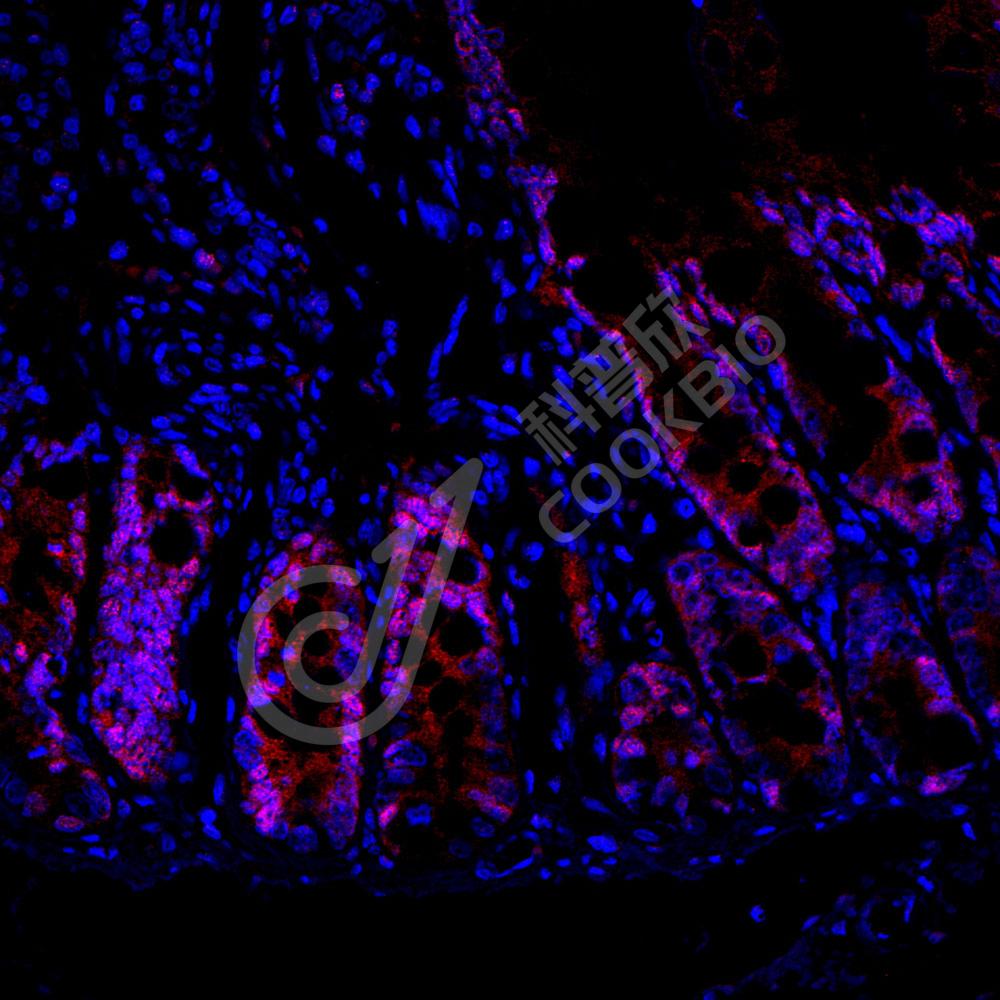

IF检测CDX2蛋白(货号 K5454503)(红色).

样品: 大鼠结肠, 4%多聚甲醛 (货号KSG1101) 固定12-24小时.

抗原修复: 柠檬酸抗原修复液(干粉, pH 6.0) (KSG1201), 高压锅均匀喷气计时2分钟.

封闭: 3% BSA(货号KSGC305010)的PBS溶液, 室温孵育30分钟.

—抗: 1: 1300稀释, 4℃ 孵育过夜.

二抗: Cy3标记山羊抗小鼠IgG (H+L) (货号KB63903), 1: 300稀释, 室温孵育1小时.